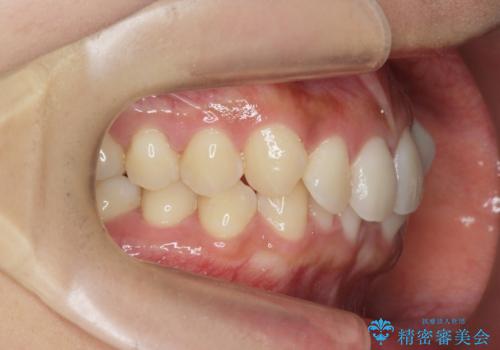

ワイヤー部分矯正治療を併用したマウスピース矯正治療

- 前歯のねじれ、深い噛み合わせ(ディープバイト)の改善を求めて来院されました。

マウスピースでは改善の難しい、歯のねじれ・ディープバイトを部分ワイヤー矯正で改善したのち、マウスピース矯正で全体の歯並びを整えていきます。

部分ワイヤー矯正を行ったことで前歯をしっかりと綺麗な歯並びへと導くことができました。